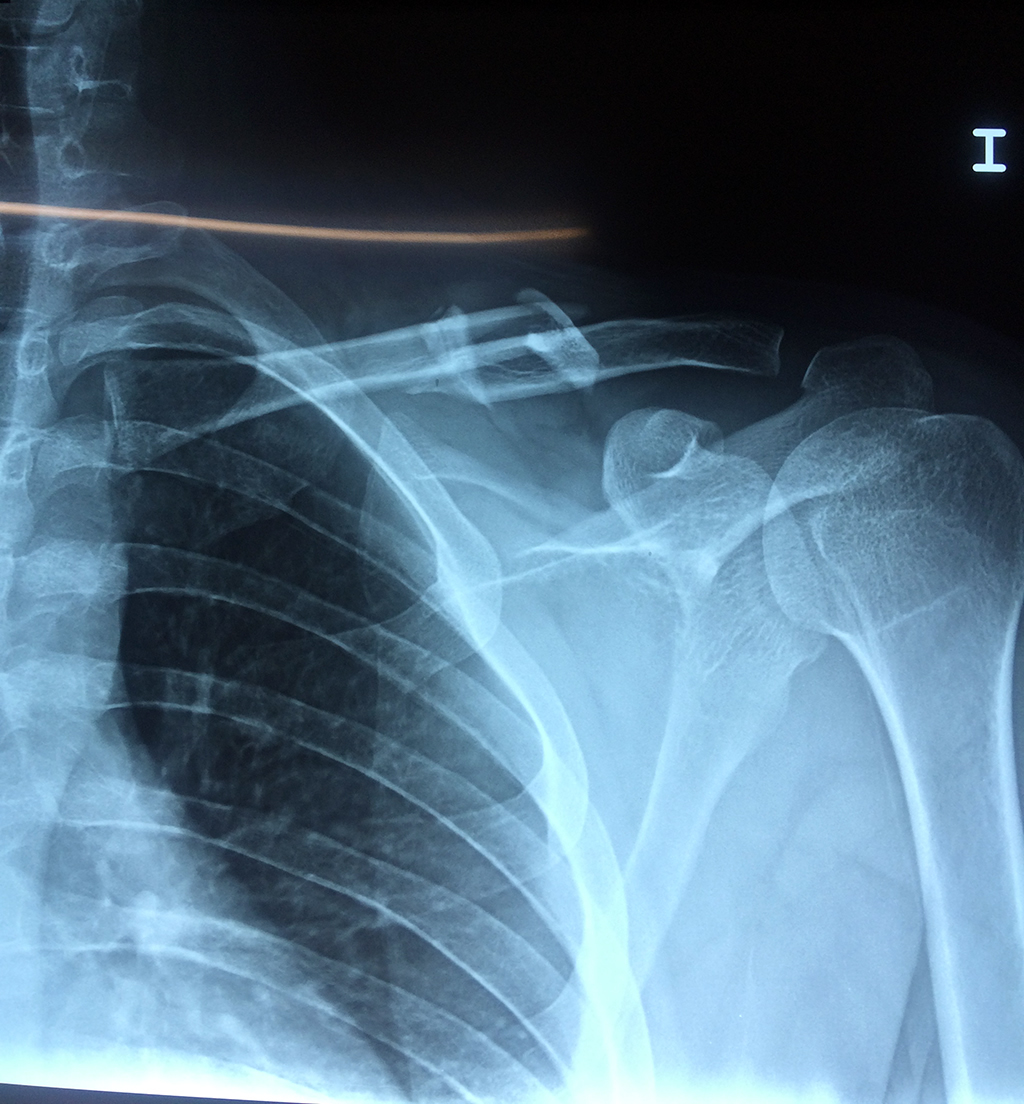

Clavicula 4

Detail Download